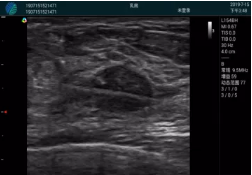

清晰顯示腺體內(nèi)低回聲快影,邊界清晰,包膜較光滑

確定進針路徑并實時監(jiān)測抽吸針與腫塊位置關系

抽吸針進入腫塊內(nèi)部進行旋切

抽吸過程中可見腫塊明顯縮小,并根據(jù)腫塊位置改變針道位置

抽吸旋切后再進行超聲復查,原腫塊區(qū)域未見殘留組織及出血